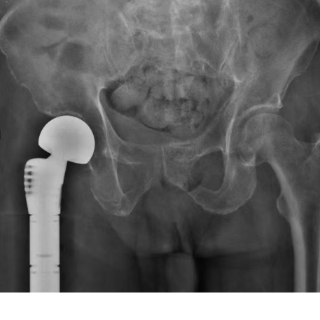

在征得家属同意后,手术由永州市中心医院首届知名专家、骨科一级顾问、主任医师叶明主刀。术中,他精准切除病变骨组织并植入人工髋关节,手术出血量远低于预期。